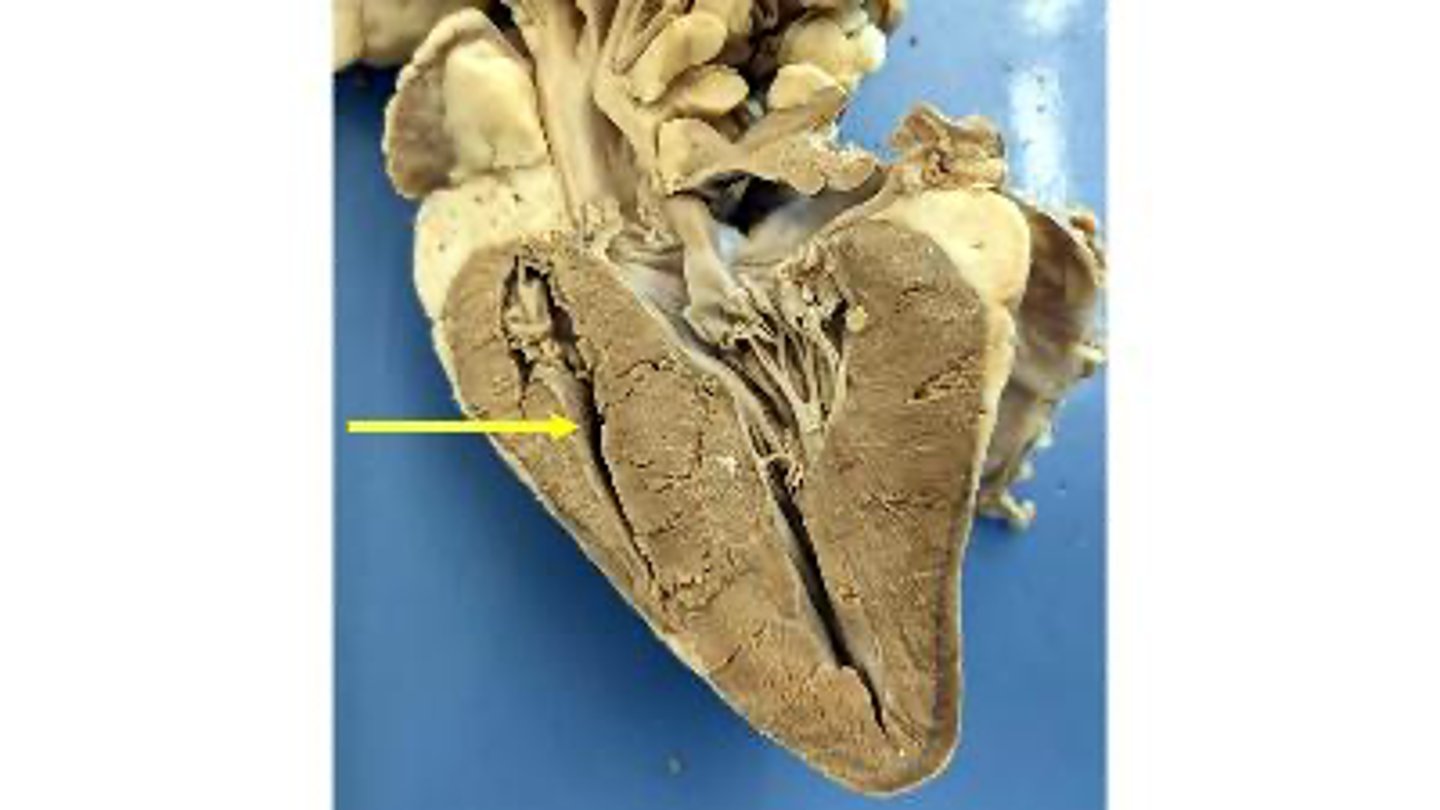

aortic valve

Name the membranous structure

right auricle

Name the ear-like structure

apex

Name the region of the organ

left ventricle

Name the chamber

interventricular septum

Name the dividing wall indicated

chordae tendineae

Name the structures

right ventricle